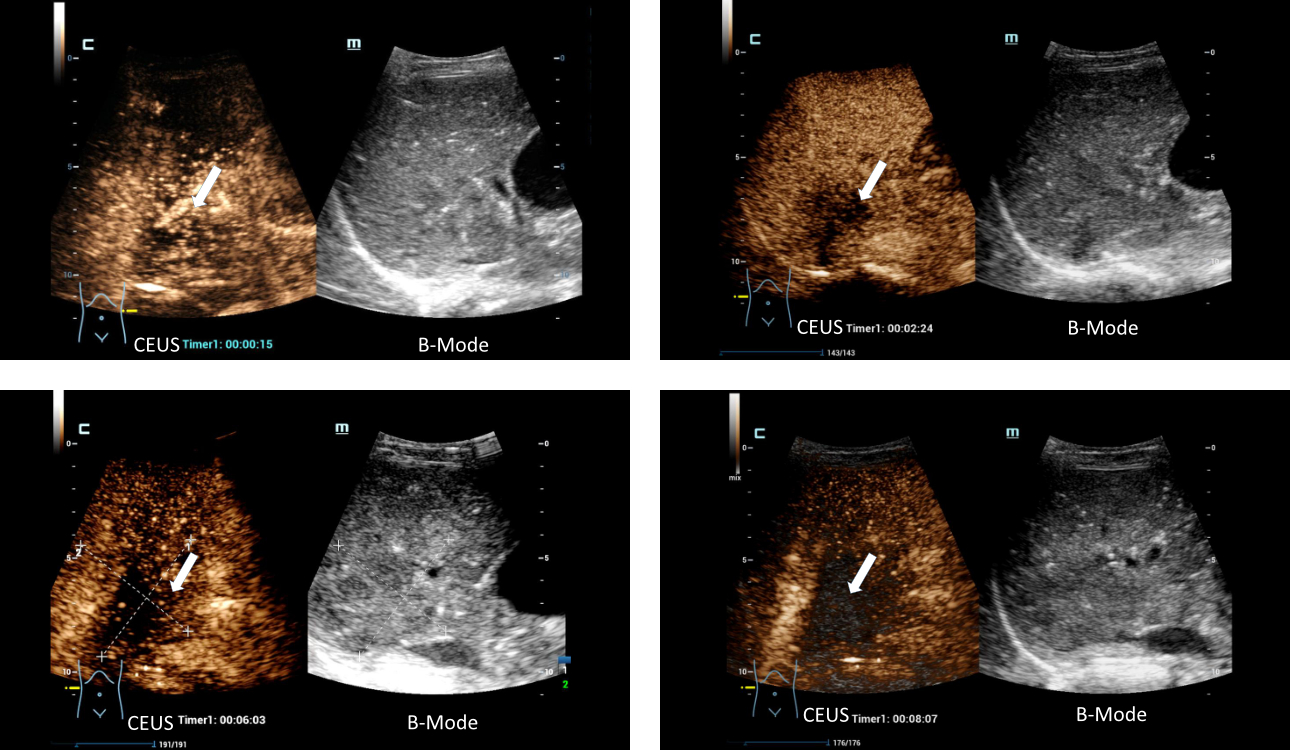

This series of images of a malignant liver lesion demonstrate a high sensitivity of signal even after 8 minutes of imaging showcasing the incredible contrast longevity achieved with HiFR CEUS.

The use of contrast agents opens entirely new possibilities. Ten seconds after injection the contrast agent reaches the lesions which then brightly ‘glow’ for 30 seconds. In this time frame, the sonographer can get a good overview of the liver. Then the glow fades and after 3 minutes the lesions once again have the same color as the surrounding healthy tissue. This used to mark the end of the liver sonography exam with contrast agents.

Now we get a second phase in which the tissue is shown in a light-dark effect. This strongly increases the quality of the clinical information and thus diagnostic confidence.

The new Mindray software, however, does something striking: for four minutes the healthy liver tissue remains brightly colored while the tumor tissue gets darker and darker – thus the tissues once again can be clearly differentiated. “Previously, we were only able to examine the liver for three minutes”, which is a rather short time frame, “but now we get a second phase in which the tissue is shown in a light-dark effect. This strongly increases the quality of the clinical information and thus diagnostic confidence.” A specific post-processing feature allows the sonographer to brighten the malignant lesions in the first 15 seconds even more – and even darker in the later stages of the phase depending on the user preferences. Certain details can even be visualized in 3D post exam.